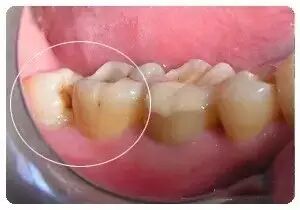

智齿因萌出位置不良,牙齿可能部分或全部被龈瓣覆盖,加上位于口腔的最内侧,刷牙的时候难以清理到,食物极易嵌塞在牙齿里,细菌滋生引起发炎,咀嚼、吞咽,开口活动疼痛加重,甚至会牵连到其他的牙齿感染。到了冠周炎的中后期,表现为口臭、舌苔变厚、智齿周围流脓等症状,甚至半边脸都会肿起,口张不开,不能进食。严重者可以伴随发烧 、头痛、便秘,淋巴结发炎肿大等。